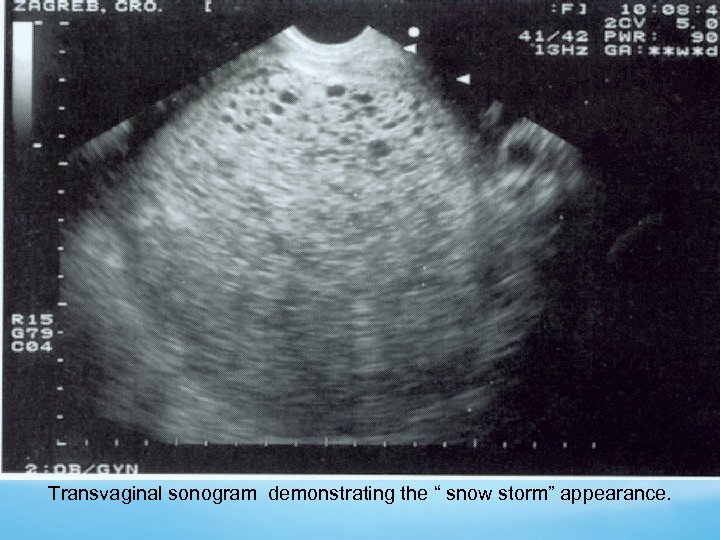

Sonography Echogenic uterine mass with anechoic cystic spaces without a fetus or amnionic sac The appearance as “snowstorm

Transvaginal sonogram demonstrating the “ snow storm” appearance.